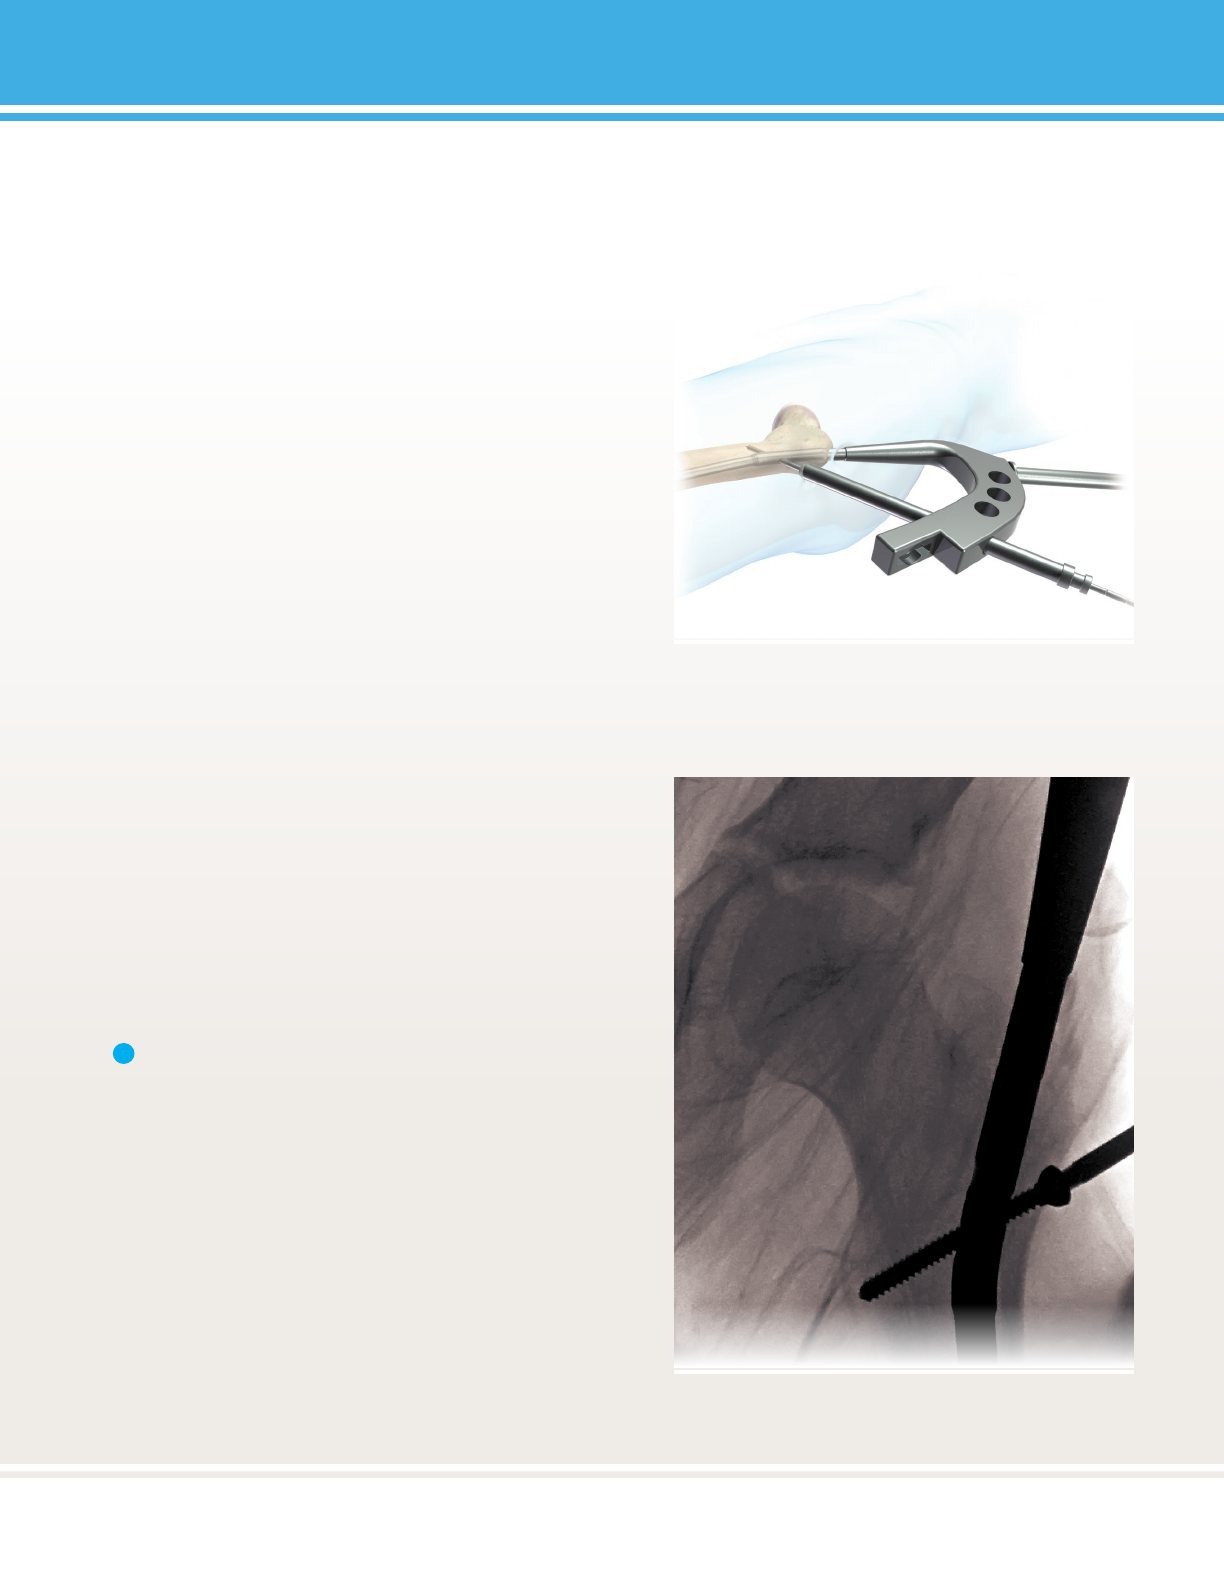

FIGURE 32:

FIGURE 33:

Note: If it is necessary to re-engage the screwdriver into

the screw head, it is recommended that the Inner Guide

Tube is reinserted into the Targeng Device rst.